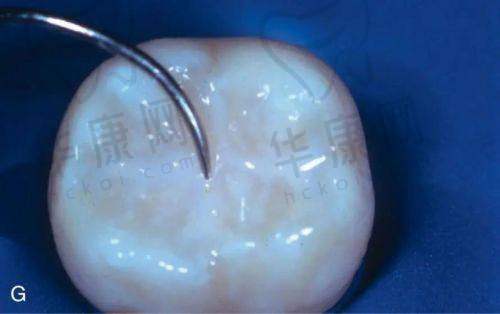

沈阳医博上诚口腔推出的儿童窝沟封42元起活动,为众多家长关注孩子口腔健康提供了实惠之选。儿童窝沟封闭对于预防龋齿有着重要意义,而沈阳医博上诚口腔在这一项目上有着独特的优势和合理的价格体系。

沈阳医博上诚口腔的儿童窝沟封价格42元起,这一价格在市场上具有特别强的竞争力。通常儿童牙齿窝沟封闭一颗的费用会因多种因素而有所不同,一般可能在40 - 80元左右。在沈阳医博上诚口腔,选择普通材质的窝沟封闭,可能就可以享受到42元起的实惠价格。而如果使用进口材质,费用相对会高一些。与其他医院相比,该口腔医院的价格更加亲民,特别多国有医院儿童窝沟封闭每颗可能在50 - 100元,私立医院价格波动更大,可能在几百元到一千元不等。沈阳医博上诚口腔以其合理的价格,为更多家庭减轻了经济负担。

同时,窝沟封闭的总费用还会受到需要封闭的牙齿数量影响。多数儿童需要处理4颗磨牙,沈阳医博上诚口腔在批量处理牙齿窝沟封闭时,也会给予一定的优惠,让家长花更少的钱,为孩子的牙齿健康提供更全方面的保护。